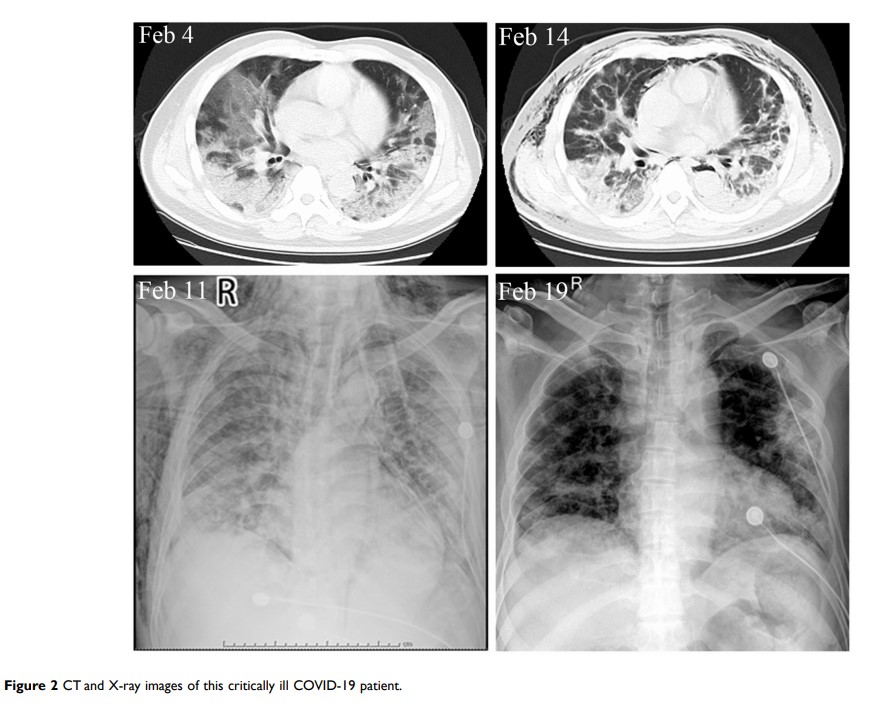

人脐带间充质干细胞用于 COVID-19 危重患者的辅助治疗:1 份病例报告